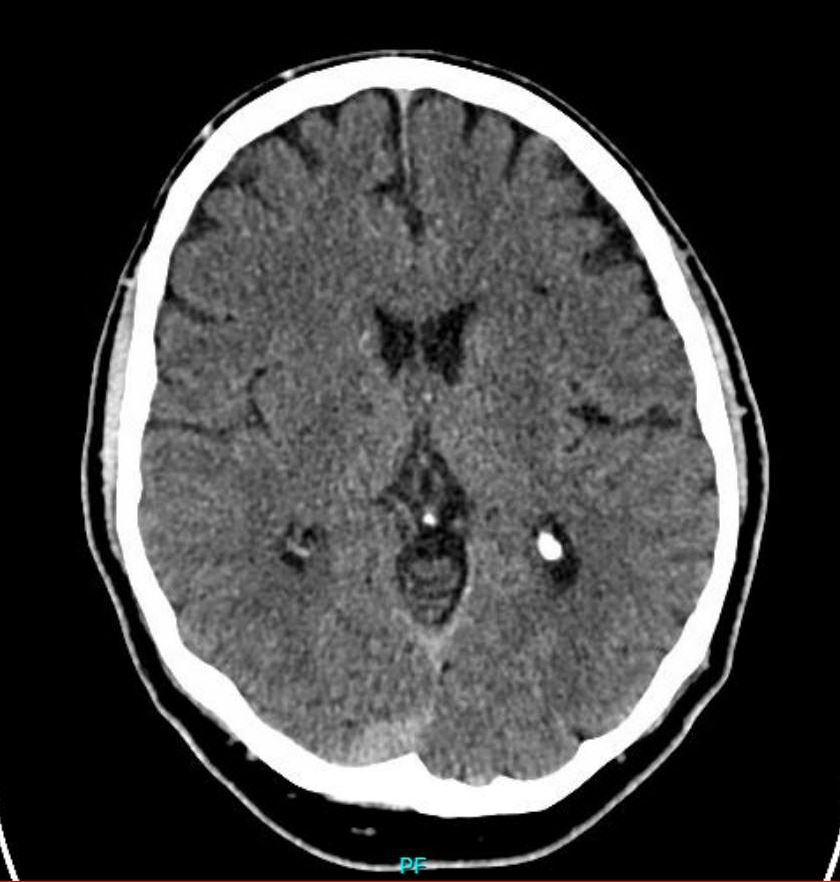

Apoplex mrt oder ct. Jedes verfahren hat seine vor nachteile. Sie haben eine hohe sensitivität im bezug auf den nachweis intrazerebraler und subarachnoidaler blutungen wie auch subduraler hämatome. Nicht kontrastierte schädel ct s stellen die bildgebung der ersten wahl dar wenn es um die abklärung eines apoplex mit unterscheidung zwischen ischämischem und hämorrhagischem schlaganfall und den ausschluss anderer intrakranieller pathologien geht. Die mrt ist der ct in der detektion von ischämien verminderte durchblutung überlegen sie kann diese früher und bereits bei geringerer größe nachweisen.

Häufig wird beim schlaganfall eine konventionelle ct des schädels durchgeführt hiermit kann man in der akutphase unterscheiden ob der schlaganfall durch eine blutung hämorrhagisch oder durch einen gefäßverschluss ischämischer hirninfarkt verursacht wurde was von entscheidender bedeutung für die weitere therapie ist. Instabil ist würde ich ebenfalls die ct bevorzugen. Beide modalitäten ct und mrt stehen hier rund um die uhr zur verfügung. Zudem zeigt sie mit größerer sicherheit als die ct ischämien des hirnstamms oder mikroangiopathische subkortikale infarkte.